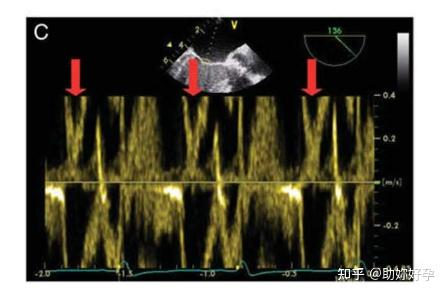

多普勒频移是不断变化的,如果它达到脉冲重复频率一半的值,多普勒图像的时间分辨率将因速度的不正确表示而受到影响。此时的多普勒频移频率称为奈奎斯特极限:

多普勒频移超过奈奎斯特极限会出现时间混叠(图 8C)。有三种主要方法可以提高时间分辨率,从而防止时间混叠: